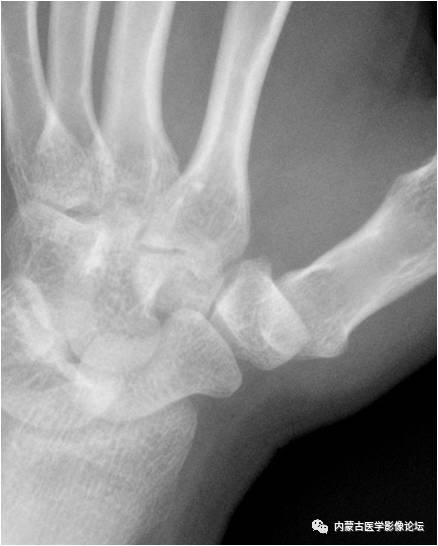

Bennett骨折:第1掌骨基底部骨折并累及掌腕关节面,可见移位的骨片。注意不应误认为副骨或籽骨。

类风湿性关节炎:双手骨质疏松,腕掌关节、桡腕关节及腕骨间关节间隙变窄,部分关节面呈虫蚀样破坏。